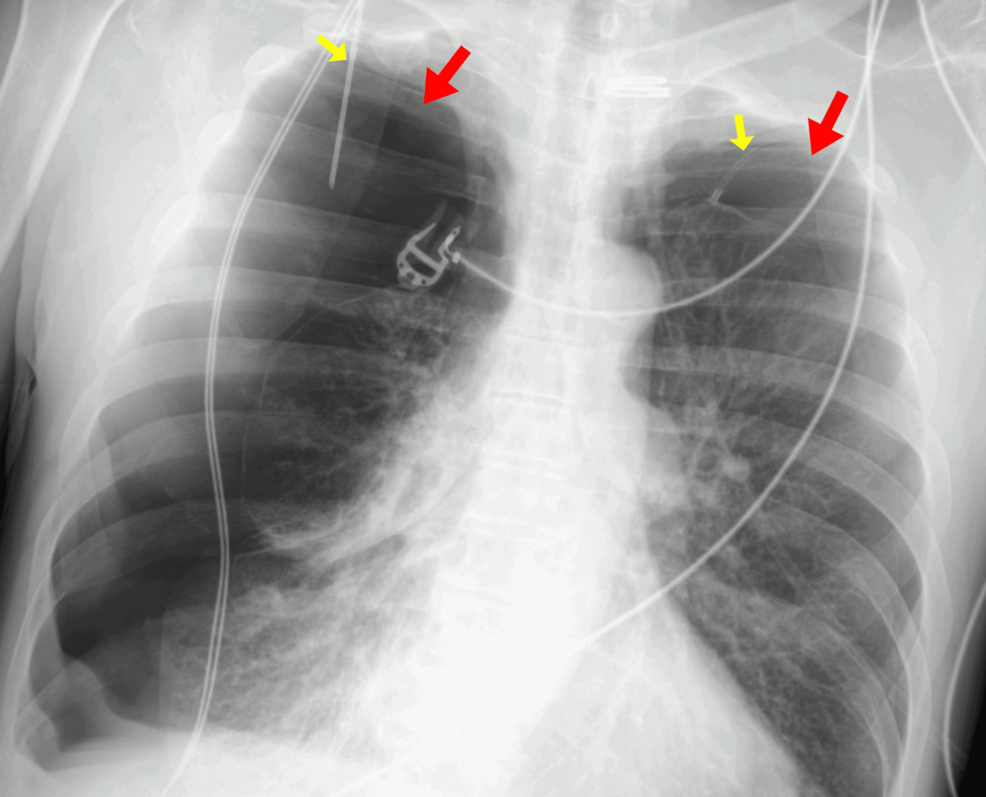

A rare complication following a minimally invasive procedure to treat a persistent air leak in the lung has been reported, highlighting the potential for unexpected and serious consequences even with established techniques. The case, detailed in a recent report, involved a patient who developed a tension pneumothorax – a life-threatening condition – on both sides of the chest after a unilateral endobronchial valve (EBV) insertion.

The development of a bilateral tension pneumothorax – meaning on both sides of the chest – following a unilateral EBV placement is exceptionally unusual. The report doesn’t detail the exact mechanism by which this occurred, but it serves as a critical reminder that even well-established procedures carry risks.